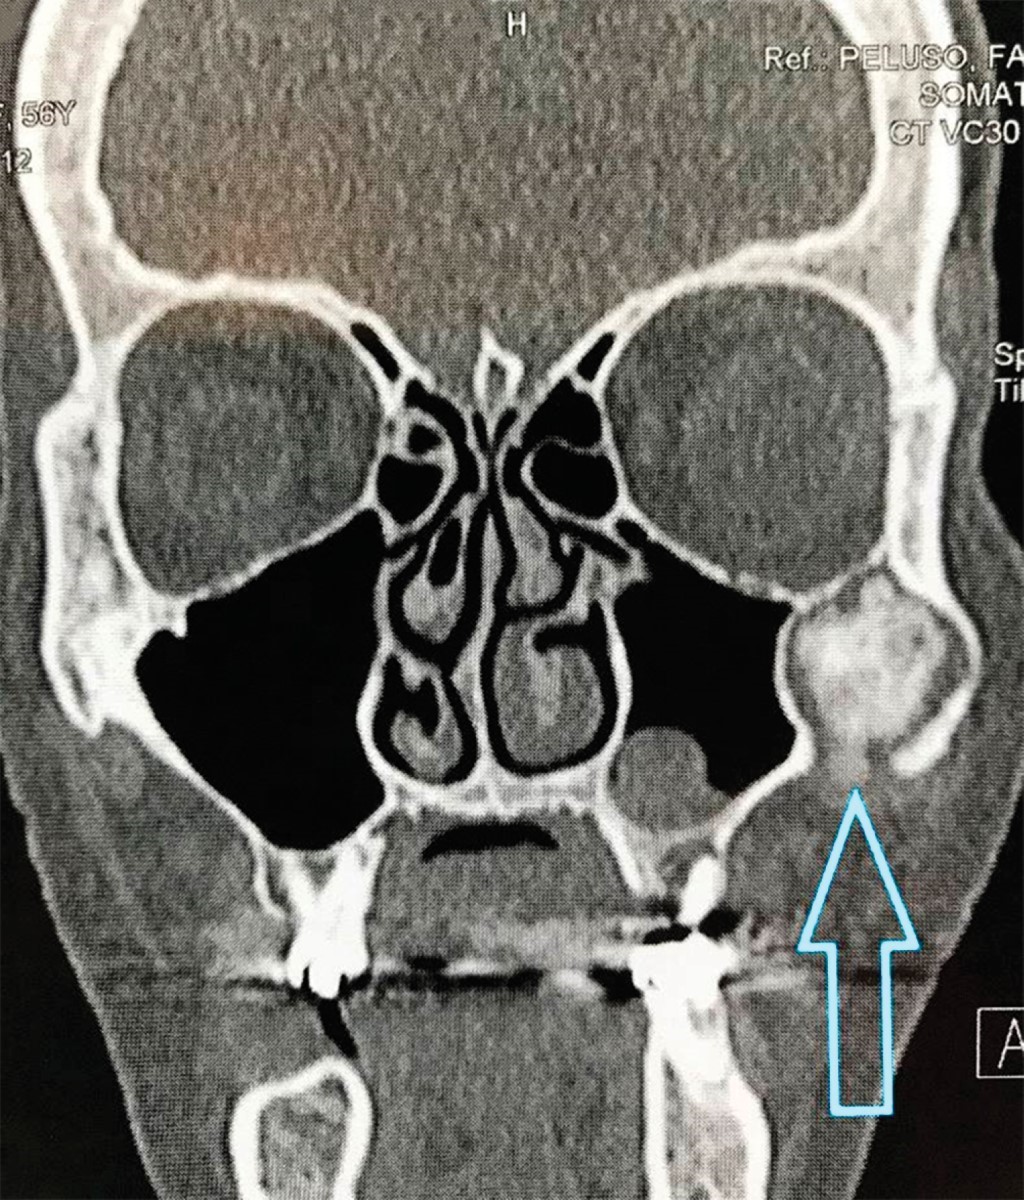

En la RMN se observa una lesión en la apófisis coronoides del lado izquierdo (Figura 4). En la ciudad de Bahía Blanca, Buenos Aires, Argentina donde desarrollamos nuestra práctica, no contamos con tomógrafo computarizado de haz cónico de Fov amplio, por lo tanto, se solicita una tomografía computarizada multislice, en la cual se verifica una lesión tumoral en la apófisis coronoides izquierda con forma de hongo, que se introduce entre el arco cigomático y el maxilar desplazando ambas estructuras (Figuras 5 y 6).

La tomografía computarizada multislice sigue siendo el estándar de oro en el diagnóstico, ya que entrega información detallada sobre la localización, tamaño, densidad y relación con otras estructuras adyacentes, información valorable para la elección del tratamiento.4,12,14,20